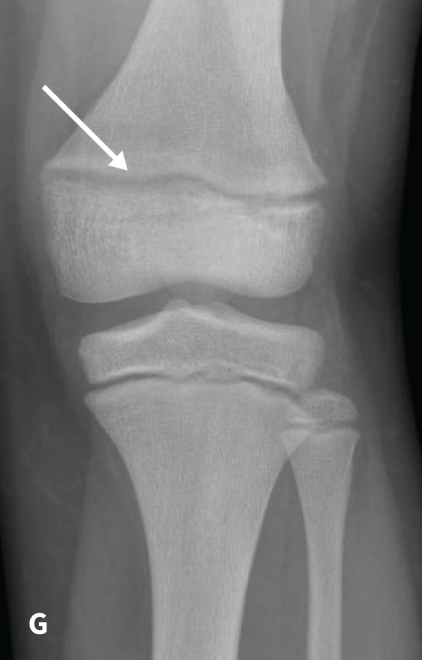

The RSS is a quantitative method that uses radiographs to assess the severity of rickets at the wrists and knees. Originally validated in nutritional rickets, the score is based on the degree of metaphyseal fraying, metaphyseal cupping, and the proportion of the growth plate that is affected. It is a 10-point scale, for which 10 represents the most severe radiographic changes due to rickets and 0 represents the absence of these changes.1

Although the severity and duration of rickets vary considerably between XLH and nutritional rickets, the radiographic features of rickets at the growth plate are similar in the two disorders, which allowed validation of the RSS in XLH. The RSS correlates with serum alkaline phosphatase (ALP) levels, a biochemical marker of rachitic activity, and this scoring system can be used to assess the radiographic response following treatment of nutritional or XLH rickets.

The RSS in XLH has been reported to range from 0 to 4.5; however, despite the smaller RSS range observed in XLH patients, inter- and intra-rater reliability are similar to those reported for nutritional rickets. Patients with XLH who had a baseline RSS ≥1.5 were shown to have more severe hypophosphatemic bone disease, including higher levels of alkaline phosphatase, and greater impairments in clinical outcomes compared with patients who had a baseline RSS <1.5.